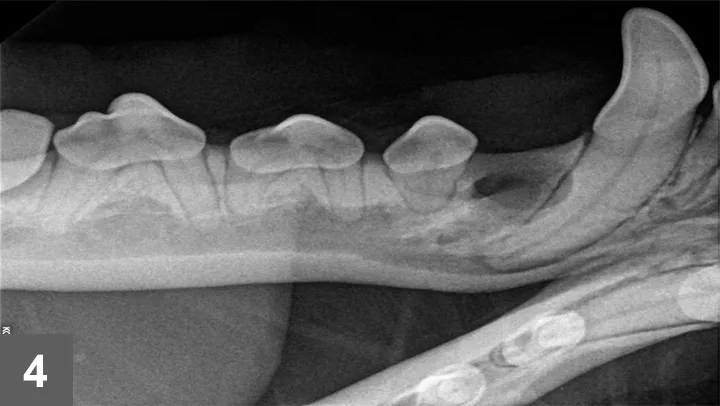

Full-mouth dental radiographs were taken (Figures 2 and 3).

Figure 2: Dental radiograph of the right rostral mandible

Missing TeethMissing teeth are more often found in brachycephalic breeds and most commonly involve the first premolar teeth.5,6 Radiographs should be taken for every missing tooth. Finding an unerupted tooth with or without an associated cyst is an important finding that could otherwise go unnoticed, thereby allowing significant structural changes to the jaw bone before outward clinical signs are noted.